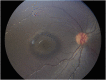

Results: A 6-year-old girl with thalassemia major who was on chronic multiple blood transfusions since 2 years of age presented with blurred vision in both eyes for 2 months. Blood reports showed very high serum ferritin levels in the range 400 to 2,250 ng/mL (checked every 3 months) since 4 years of age. She was on oral iron chelator deferasirox for 2 years, which was stopped a month ago. Fundus examination of both eyes showed a characteristic bull's eye macula with a purplish hue in the outer ring probably due to iron deposition. The center of the bull's eye had a beaten bronze appearance.